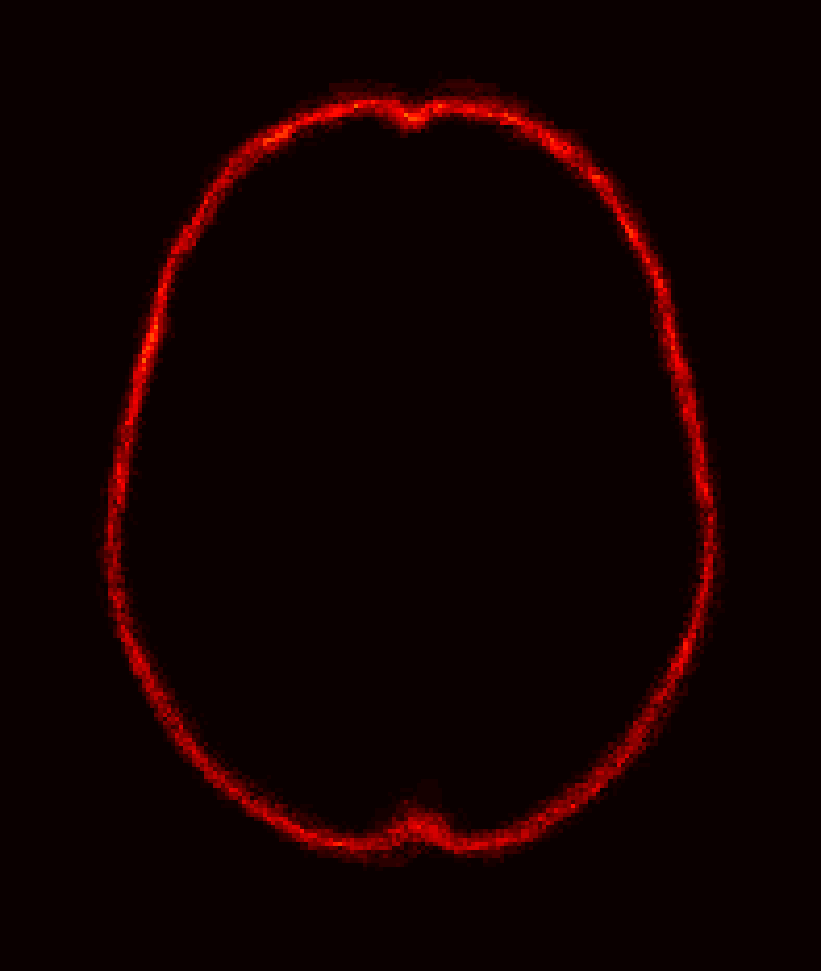

Fig. 1 shows example images from each dataset to illustrate image variability. IBSR and LPBA40 contain images from normal subjects and include large portions of the neck; BRATS has very low out-of-plane resolution; and the TBI dataset contains large pathologies and abnormal skulls.

Refer to caption

Figure 1: Illustration of image appearance variability on a selection of images from each (evaluation) database. From top to bottom: IBSR, LPBA40, BRATS and TBI.